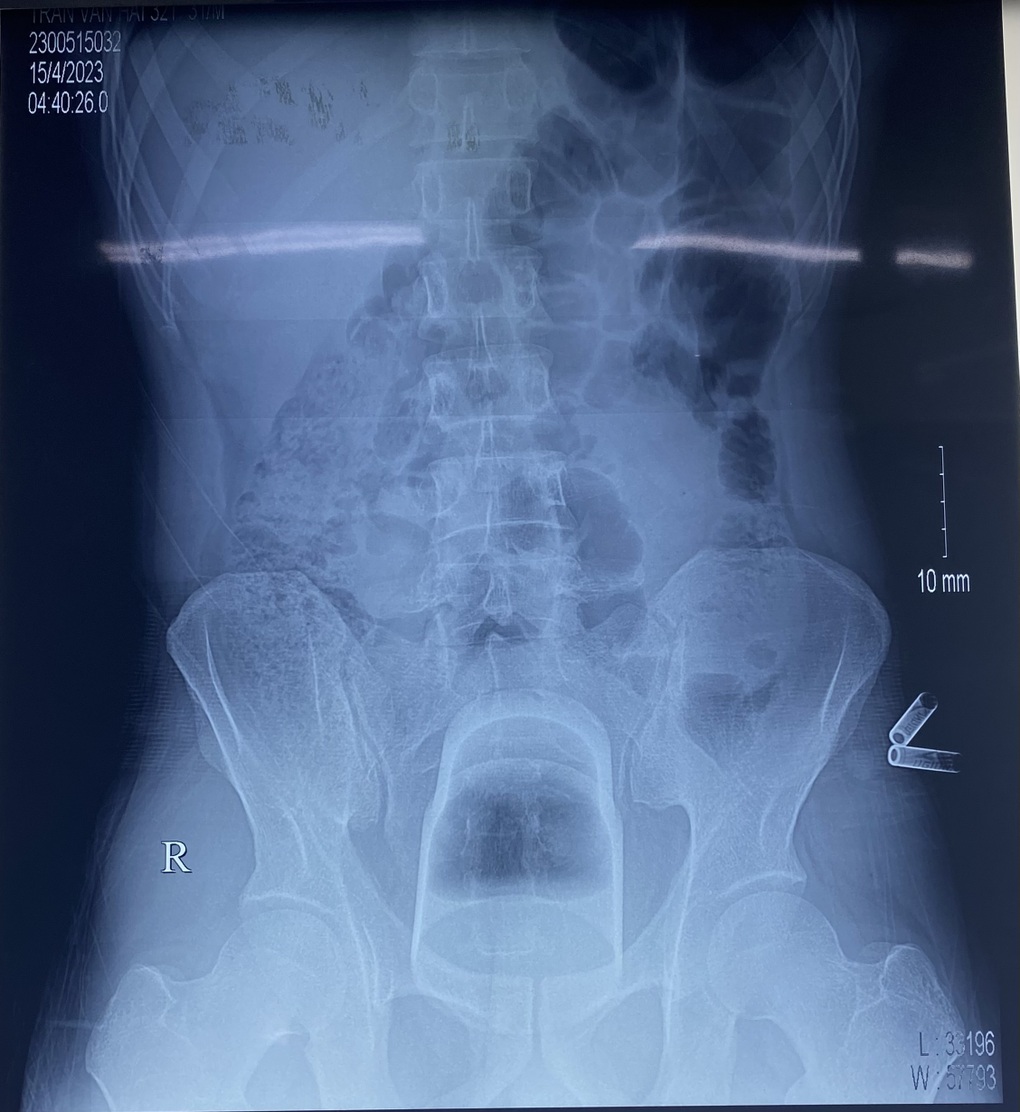

Hình ảnh phim chụp X-quang cho thấy, có dị vật nằm sâu trong trực tràng của bệnh nhân.

"Dị vật có đường kính 7cm, dài 12cm nằm kẹt rất sâu trong trực tràng và kẹt chặt vào khung chậu, không thể lấy được qua đường hậu môn nên chúng tôi phải mổ trực tràng để lấy dị vật, đưa đại tràng sigma ra ngoài làm hậu môn nhân tạo", BS Tâm cho biết.

Hình ảnh dị vật nằm kẹt sâu trong trực tràng bệnh nhân (Ảnh phim chụp X-quang).